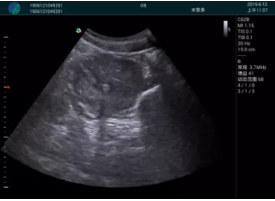

清晰顯示孕囊,通過軟件包計算孕齡7w+6d

M20實時引導,術(shù)中清晰顯示孕囊被破壞和抽吸針的過程,清晰顯示吸引針

抽吸結(jié)束后縱切子宮,孕囊已被完全抽吸,未見明顯殘留

橫切子宮,發(fā)現(xiàn)右側(cè)宮腔靠近宮角處有少許脫模樣殘留